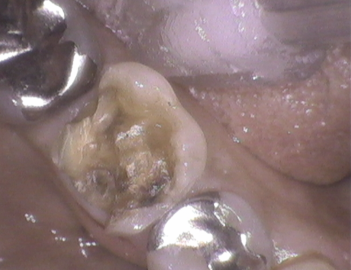

金属が外れて来院。金属、樹脂等の詰め物の選択はありましたが、1日で治療を完了したい旨に添い、レジン充填。

ちょっとヴォリュームは大きいけれど

ちょっと体積は大きかったです。隣接歯とのコンタクトをしっかりとり、噛み合わせを確認。レジン充填ですから、咬耗が今後生じます。管理していきましょう。